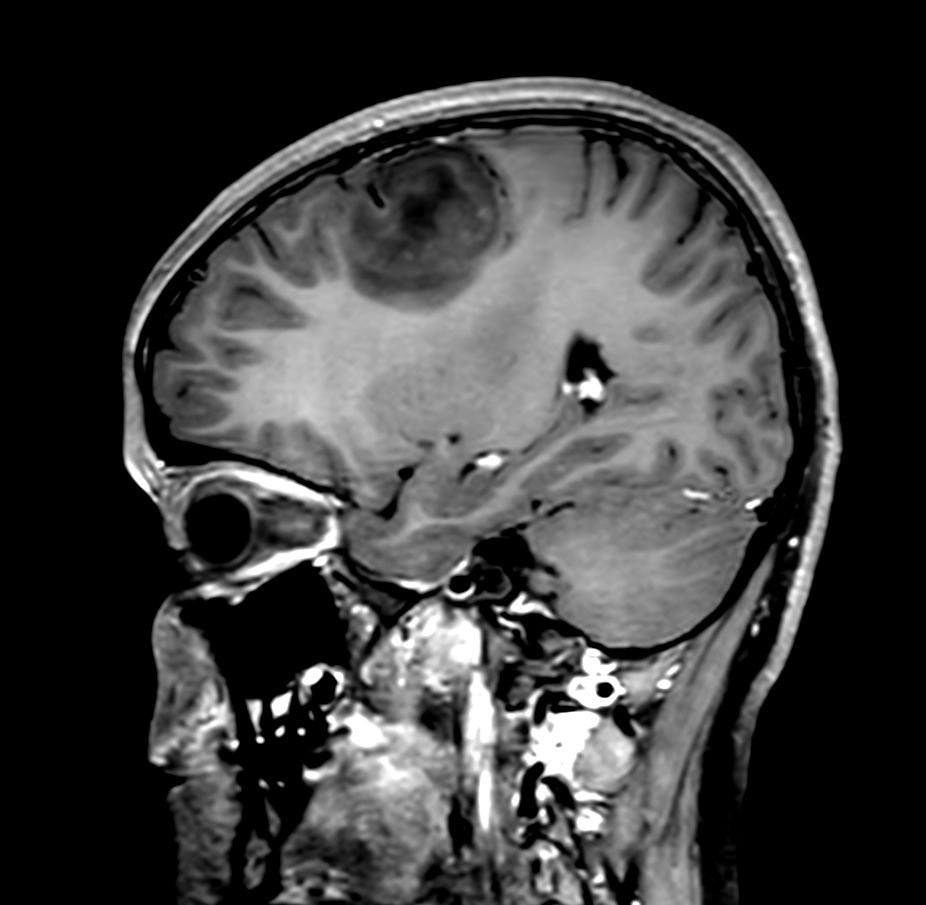

Patient with a brain lesion. ExamCard includes MultiVane XD for motion-free imaging in short scan time, Compressed SENSE to shorten exam time, SWIp to enhance contrast for deoxygenated (venous) blood or calcium deposits, a high resolution 3D FLAIR sequence enabling reformats in any plane without loss of resolution, diffusion to achieve high contrast between background and lesions, pCASL to visualize brain perfusion and functional physiology in a non-contrast manner, dynamic multi-slice T2* perfusion for quantitative analysis, and spectroscopy for a non-invasive measurement of biochemical changes in the brain.

Sagittal 3D T1w TSE +gado Compressed SENSE